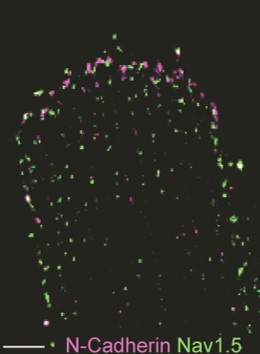

Distinct subcellular pools of Nav1.5-based sodium channels within the cardiomyocyte have been demonstrated, in particular at the intercalated disc and lateral membrane regions. Within these domains, Nav1.5 channels are not homogeneously distributed but rather grouped in clusters of various sizes and densities. Furthermore, different interacting proteins associate with Nav1.5 at these distinct subcellular domains, and are thought to contribute to the differences in channel density and/or kinetics observed between these areas. Sodium channels located at the lateral membrane are associated with the syntrophin-dystrophin complex. We have previously shown that mice lacking the last three amino acids of Nav1.5 essential for the interaction with the syntrophin-dystrophin complex show sodium current reduction exclusively at the lateral membrane (Shy et al. Circulation 2014). Nav1.5 channels in the intercalated disc region (which is devoid of syntrophin) interact with SAP97, plakophilin-2, desmoglein-2 and coxsackie and adenovirus receptor (CAR).